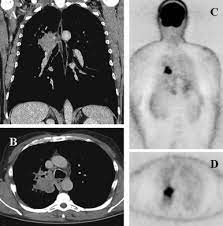

Pet/ct, which is a combination of positron emission tomography (pet) with computerized tomography (ct), is a powerful, essential tool for cancer detection and diagnosis.

A Large Scale Ct And Pet Ct Dataset For Lung Cancer Diagnosis Lung Pet Ct Dx The Cancer Imaging Archive Tcia Public Access Cancer Imaging Archive Wiki from wiki.cancerimagingarchive.net Bone scans look for cancers that may have spread (metastasized) from other places to the bones. Pet/ct imaging helps to determine where a primary tumor is located. They are also used to assess if treatment is being effective in eliminating cancer. It provides 3d color images of the cells of your body. Cancer, including breast cancer, lung cancer and thyroid cancer. Then because of its high degree of specificity, pet/ct helps with radiation treatment planning. It may help identify a variety of conditions, including many cancers, heart disease and brain disorders. Brain disorders, such as brain tumors, epilepsy, dementia and alzheimer's disease.

Help diagnose and manage central nervous system disorders such as depression, epilepsy, alzheimer's and parkinson's disease. Because of this high level of chemical activity, cancer cells show up as bright spots on pet scans. Coronary artery disease, heart attack or other heart problems. With that being said, not all cancers can be detected by pet. A pet scan is similar to a ct scan; Pet is primarily used to diagnose cancer, cardiovascular disease, and neurologic disorders. Before the scan, you receive an injection of a tracer called radioactive glucose. Pet scans can help detect cancer and how far it has spread. The pet/ct scanner produces an image of the anatomy fused with the functional images of the use of sugar by cells. Doctors often order pet scans to stage a cancer or to assess whether treatment is working. Do all cancers show up on pet scan? The scans can also evaluate the occurrence of colorectal, lymphoma, melanoma, and pancreatic tumors. Brain disorders, such as brain tumors, epilepsy, dementia and alzheimer's disease.

Pet/ct, which is a combination of positron emission tomography (pet) with computerized tomography (ct), is a powerful, essential tool for cancer detection and diagnosis. Pet/ct imaging helps to determine where a primary tumor is located. Positron emission tomography (pet) scan. The parts of the body that need the most energy and the energy they use is sugar (also called glucose). So, what tests are done to check for cancer?